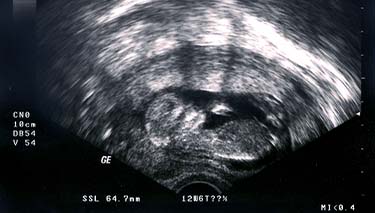

The ultrasound will pick up images of your baby's organs in a series of cross sections. This can be confusing at first, until you become used to the images and your eyes adjust. Your baby's bones will be white on the screen and the amniotic fluid will appear as black. Their tissues will be grey and have a speckled appearance.

- Measurements of your baby's head, biparietal diameter, length and a measurement of their femur (long bone in the thigh) will also be taken. These measurements are compared with the average for babies of the same gestation.